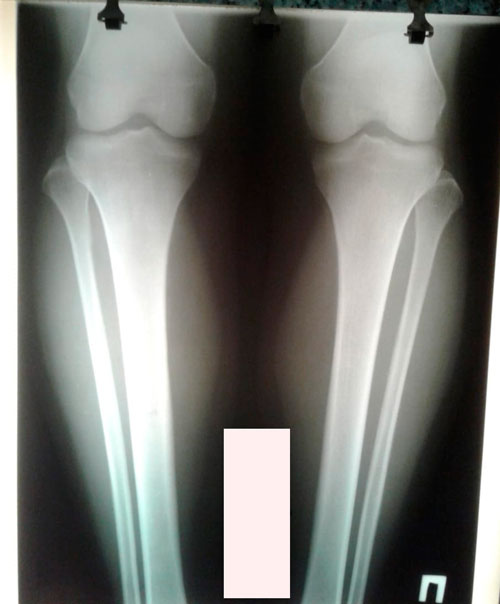

Дата операции - 04.03.2019г.

Дата снятия аппаратов - 18.06.2019г.

Срок сращения - 104 дня.